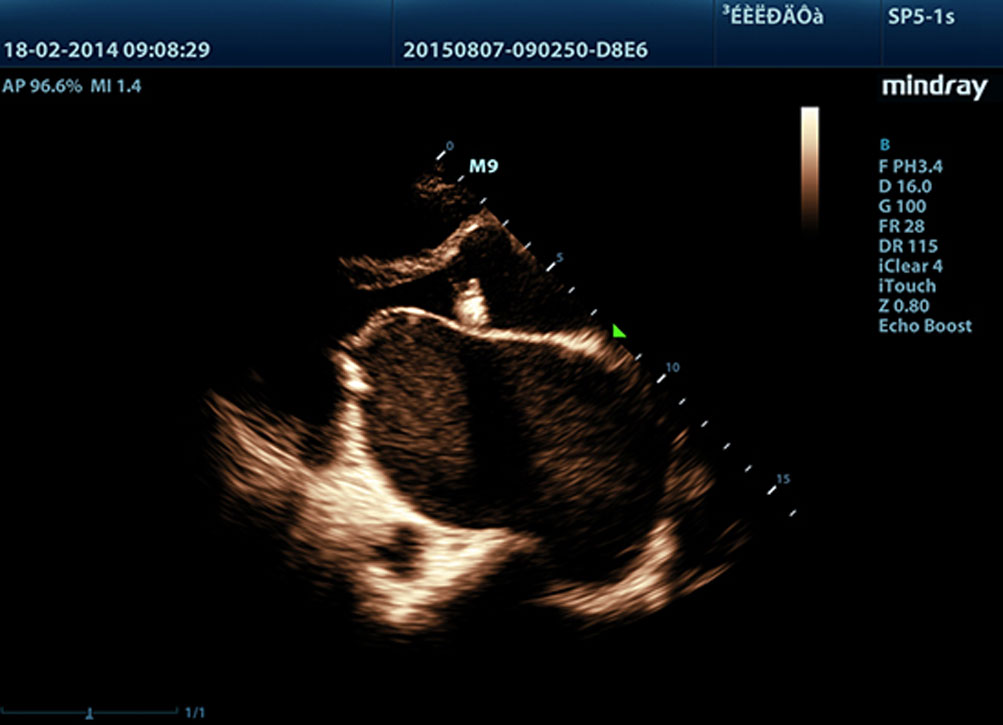

LVO z badaniem wysi?kowym

Mo?liwo?ci premium systemu M9 pozwalaj? na zwi?kszenie kontrastu lewej komory podczas badaÅ wysi?kowych, wzmacniaj?c rozrÃģ?nienie pomi?dzy tkank? mi??nia sercowego a przep?ywem krwi. Umo?liwia to lepsz? wizualizacj? wsierdzia. Funkcja Stress Echo w aparacie M9 obejmuje kompletny pakiet dla obci??enia farmakologicznego i?wysi?kowego. Pakiet ten jest wspierany przez elastyczny system raportowania, ktÃģry mo?na dostosowa? do PaÅstwa indywidualnych potrzeb.